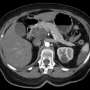

The pancreas, a vital organ located behind the lower part of the stomach, plays a crucial role in producing hormones that regulate blood sugar and enzymes that aid in digestion. Yet, when it becomes cancerous, the consequences can be severe. Medical professionals emphasize the importance of recognizing symptoms early, as pancreatic cancer has one of the highest mortality rates among cancers.